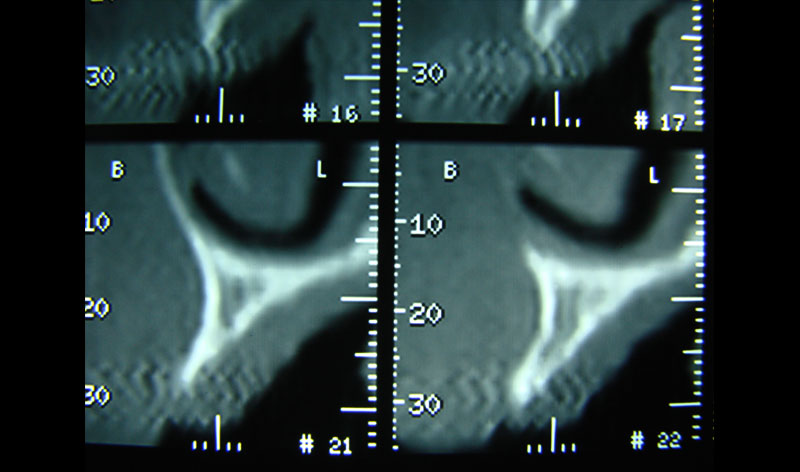

Existen muchas situaciones donde la pérdida y la atrofia ósea son tan graves que nos obligan a recurrir a la cresta iliaca del paciente, para conseguir el volumen óseo necesario para la correcta reconstrucción del maxilar. Así, la colocación de implantes será posible a los 3 meses.